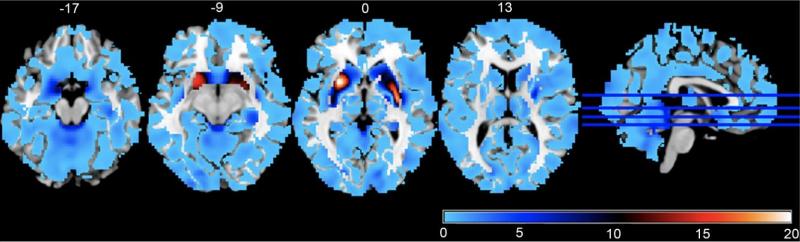

上圖是精神分裂症的一個風險基因位點與全腦灰質體積關聯性的3維空間分佈;紅色越深表示統計顯著性越高,其次是黃色、綠色,統計顯著性最低是藍色。右圖是最顯著的腦區(殼核)灰質體積與全基因組變異位點關聯性的曼哈頓圖。結果按照染色體序號排列。

大腦截面圖,藍色表示和風險位點的相關性不顯著,紅色表示顯著